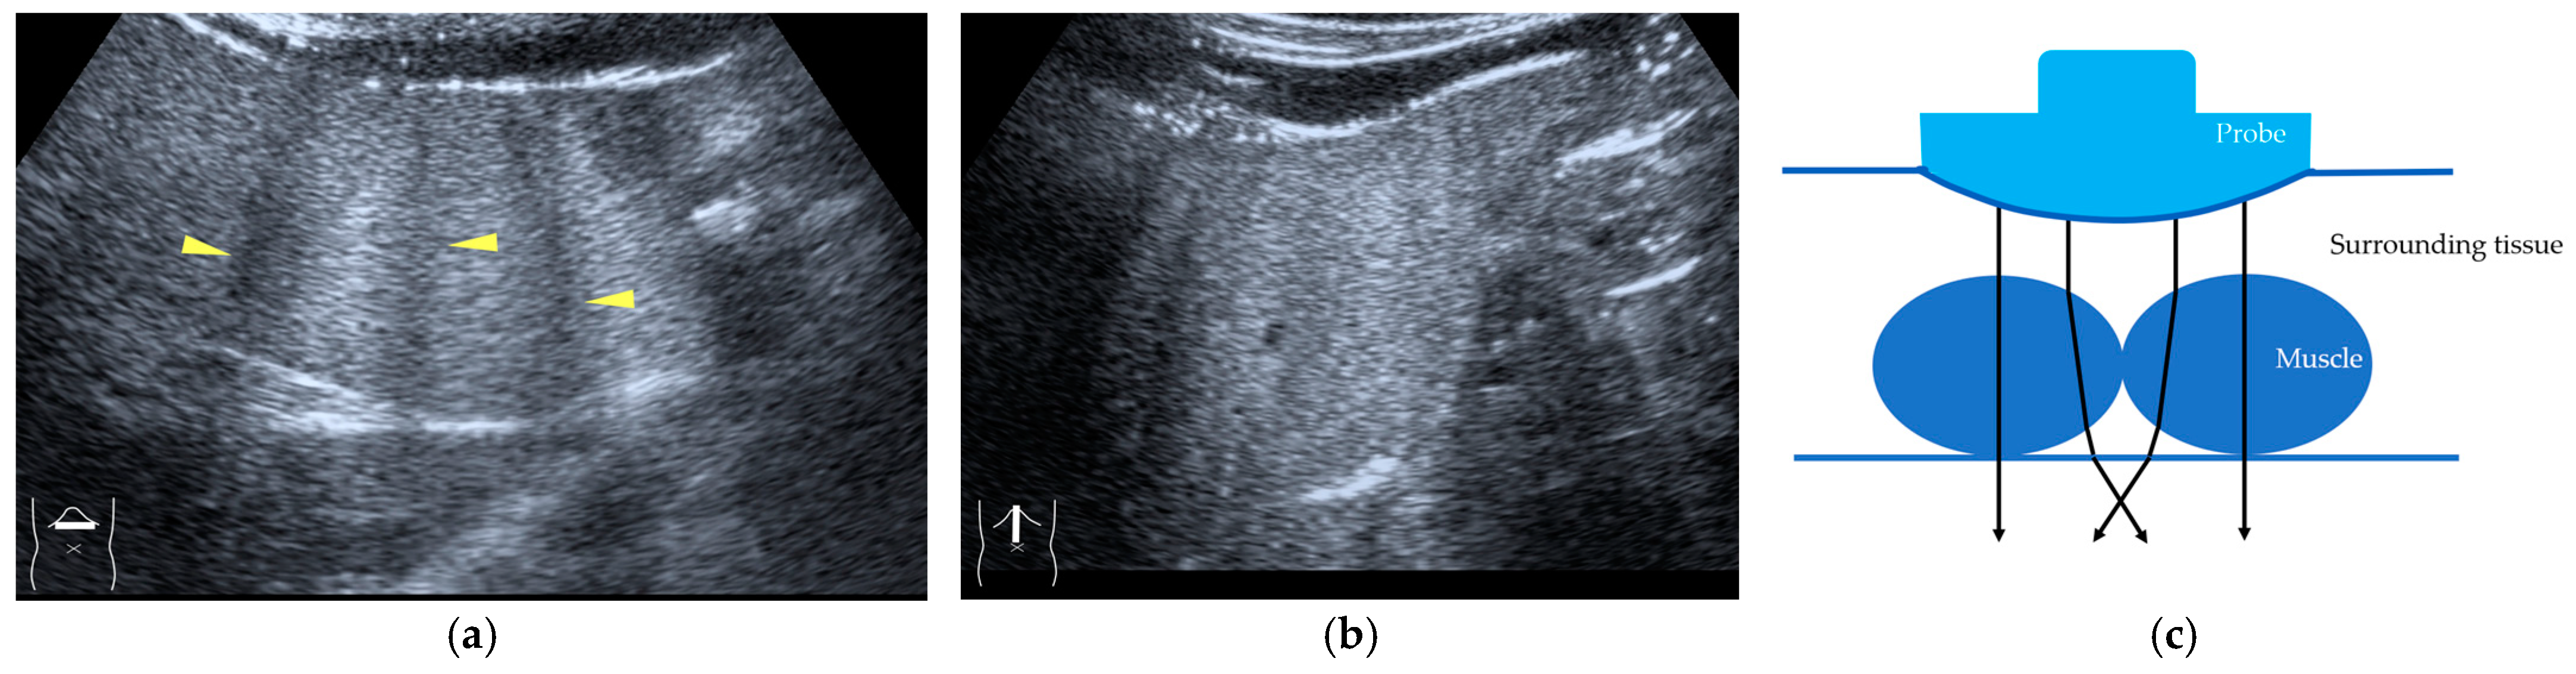

Figure 5.

Refraction artifact (3): hypoenhanced lines due to US refraction. (a) CEUS shows many hypoechoic lines throughout the liver parenchyma via transverse scanning (arrowheads). (b) The liver’s left lobe shows none of the lines seen in (a) via sagittal scanning. (c) A schematic drawing of sound refraction due to rectus abdominus via transverse scanning plane. The US beam changes direction twice, first at the surrounding tissue–rectus muscle interface, then at the rectus muscle–surrounding tissue interface.